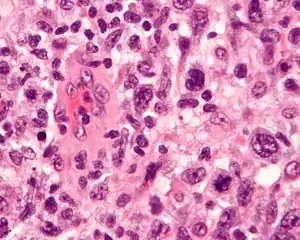

| Micrograph of an anaplastic large cell lymphoma. H&E stain. | |

Anaplastic large cell lymphoma is characterized by "hallmark" cells and presence for CD30. Integration of this information with clinical presentation is crucial for final classification and management of patients.

The classification acknowledges the recognition of large cells with pleomorphic nuclei and abundant cytoplasm. Also required in the diagnosis is immunophenotypic evidence that cells are T lymphocytes, such as the expression of immunologic markers CD3 or CD4, but CD30 expression must be present in all neoplastic cells. Out of the 4 types of ALCL, one subtype of systemic ALCL expresses the protein anaplastic lymphoma kinase (ALK); the other types of ALCL do not express ALK.

The hallmark cells are of medium size and feature abundant cytoplasm (which may be clear, amphophilic or eosinophilic), kidney shaped nuclei, and a paranuclear eosinophilic region. Occasional cells may be identified in which the plane of section passes through the nucleus in such a way that it appears to enclose a region of cytoplasm within a ring; such cells are called "doughnut" cells.

On histological examination, hallmark cells must be present. Where they are not present in large numbers, they are usually located around blood vessels. Morphologic variants include the following types: